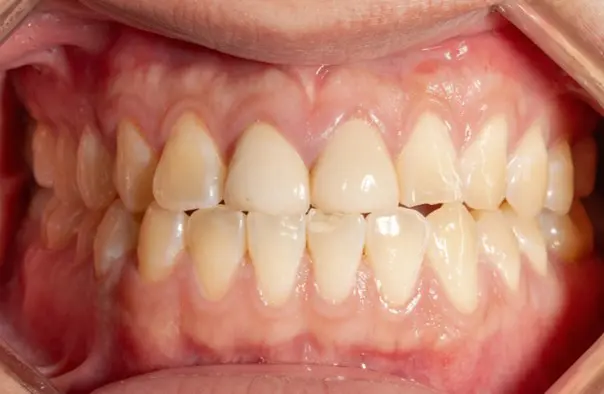

Crossbite

Before

After